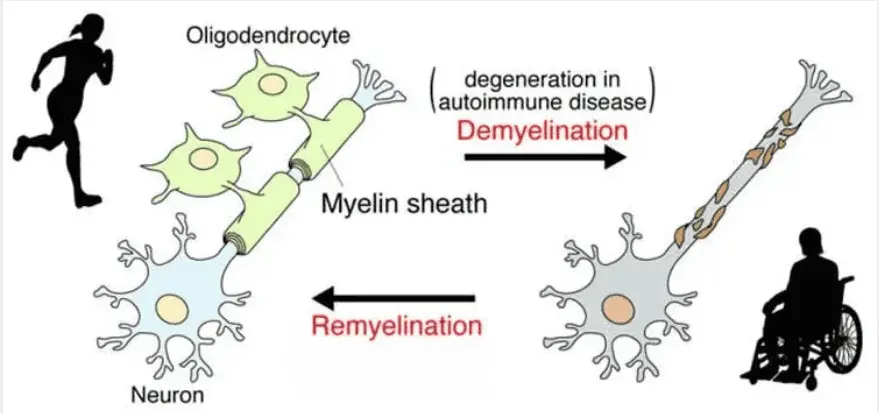

Why MS OCCURS

MS is an autoimmune disease that damages the myelin coating around nerve fibres, causing disruption of nerve signals

This disruption can cause problems with vision, movement, strength, coordination and thinking

In a healthy neuron, myelin protects nerve fibres, like insulation around a wire

Patients with MS exhibit damaged myelin and nerve fibres (demyelination)

None of the drugs seek to repair or reverse the damage of myelin, (remyelination),which may stop progression reverse the course of MS